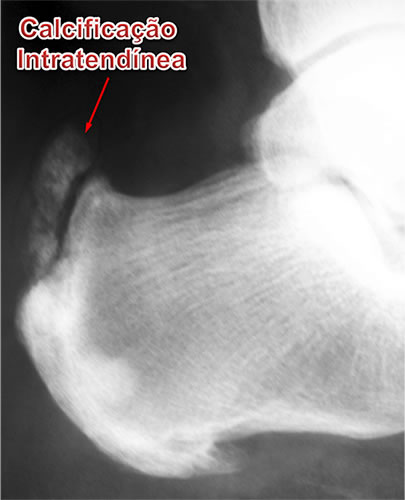

- Calcificação Intratendínea (Esporão do Tendão de Aquiles)

A calcificação intratendinea, popularmente chamada de esporão do tendão de Aquiles, forma-se por uma alteração celular degenerativa das fibras do tendão. Isto ocorre pela alternância, durante um longo período de tempo, entre os processos de inflamação, micro ruptura e reparo local. Portanto, a constante tentativa de cicatrização de uma lesão crônica do tendão leva à sua degeneração e calcificação local de suas fibras.

O diagnóstico de tendinite e tendinose do tendão de Aquile é feito pelo relato da história pelo paciente e através do exame físico ortopédico. As radiografias do tornozelo servem para avaliar as calcificações ao longo do trajeto do tendão, assim como erosões ósseas e a deformidade de Haglund do calcâneo quando presentes.